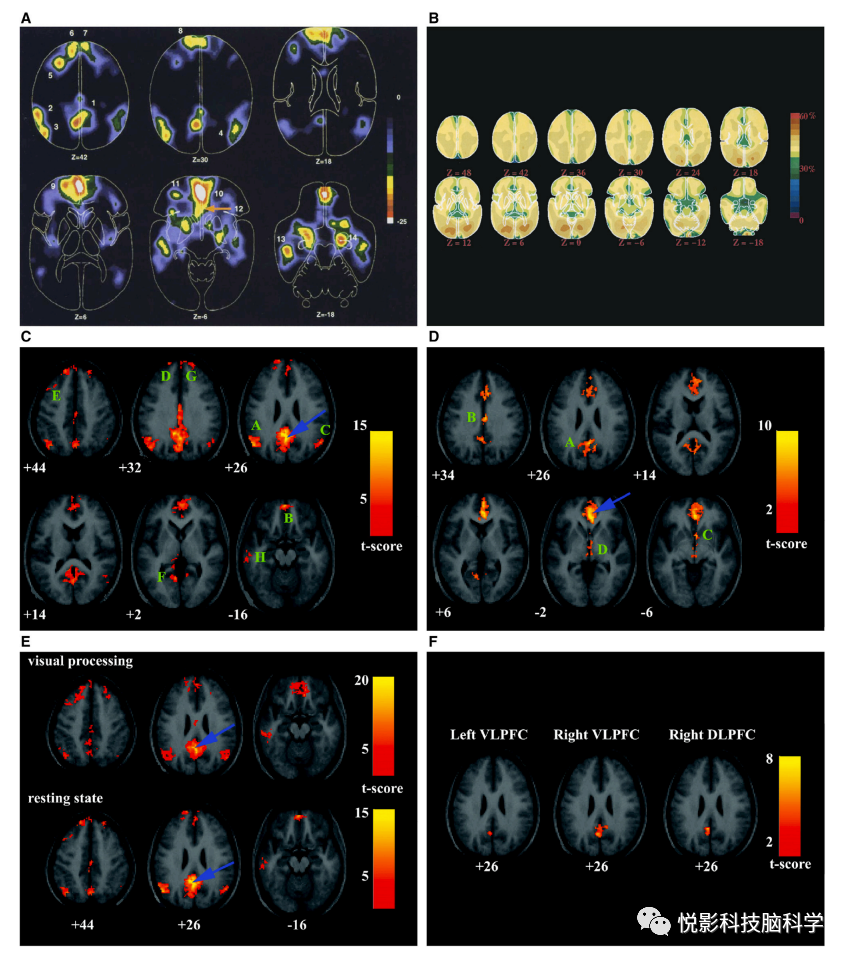

DMN的发现起源于一个令人惊讶的发现,即大脑中一组常见的区域在注意外部刺激时受到抑制。1997年,舒尔曼和他的同事发表了一项荟萃分析,总结了他们自20世纪80年代末以来获得的多个正电子发射断层扫描(PET)数据集的研究结果。参与者被要求执行一系列任务,涉及在主动、被动和注视条件下操纵注意力、记忆和语言。在九项关于人类视觉信息处理的研究中,他们检查了在主动任务期间与被动观看相同刺激阵列的实验之间血液流量减少的一致性。在主动任务期间表现出持续下降的大脑区域包括后扣带回/楔前叶(布罗德曼区 [BA] 31/7)、左下顶叶皮层(BA 39/40)、左背外侧额叶皮层(BA 9)、左 外侧额下皮质 (BA 10/47)、左侧颞下回 (BA 20)、内侧前额皮质 (mPFC)(BA 8、9、10 和 32)和右侧杏仁核(图 2A)。Mazoyer 及其同事随后进行的 PET 研究证实了这些发现;失活的共性使得作者提出,有意识休息状态下的大脑活动可能是由一个大规模的异模态关联顶叶和额叶皮质区域网络来维持的。

在 2001 年发表的一项开创性研究中,Raichle 及其同事调查了 PET 研究中观察到的通常失活的区域是否可能在“休息”时表现出区域性增强的活动。他们使用定量代谢和循环测量来确定与任务相关的活动减少是否源于以下原因:静息状态下的激活。然而,正如他们所指出的,“激活区域由于它们的缺失而显得很明显。”令人惊讶的是,与平均氧提取分数的所有显着偏差都是失活,并且几乎完全在视觉系统中观察到(图 2B)。然而,在基于任务的 PET 和功能磁共振成像研究中,最初被确定为失活的大部分大脑区域在这里都缺失了。因此,与任务相关的失活似乎并不是由静息状态下的增强激活引起的,并且证明失活区域在基线状态下可能处于紧张性活动的证据难以捉摸。这项研究的一个重要方面是人类大脑功能研究中的一个核心问题的框架,这导致作者创造了“默认模式”这个术语。事实证明,这个术语非常有先见之明和富有洞察力,并已被广泛使用。在神经科学领域被采用。与许多有影响力的研究一样,这项工作提出的问题比它回答的问题更重要。“默认模式”是脑成像研究中使用的基线条件的产物吗?PET 研究中显示失活的大脑区域是否构成了相互连接的节点的连贯网络?默认模式的认知功能是什么?如何通过实验任务操作直接研究它们?

事实证明,解决这个问题的不同方法更容易处理。1995年,Biswal等人报道,在手指运动任务中,感觉运动区在自发的低频(<0.1赫兹)波动中也显示出同步的时间反应。有两个观察结果突出:低频波动中的相关性可以用来探测功能大脑网络,这些波动反映了任务相关区域的共同激活。在此期间,在斯坦福大学,我们开始在健康的成年人对照组和抑郁症或阿尔茨海默病患者中获得全脑静息状态的功能磁共振成像。在获得与障碍相关的项目数据的同时,迈克尔·格雷西乌斯和我决定检查与健康对照组的工作记忆任务相关的大脑网络。一个关键目标是将与任务相关的停用与功能连通性分析联系起来。我们找出了表现出一致失活的大脑区域,并检查了它们是否形成了一个连贯的内在网络,以及这个网络在认知过程中是如何受到调节的。后扣带皮质(PCC)作为自然的种子目标出现,一方面是基于在健康成年人的认知功能磁共振研究中观察到的与任务相关的失活的常见部位,另一方面是在阿尔茨海默病的PET研究中观察到的功能损害。我们定义了在工作记忆任务中表现出活动减少的PCC和mPFC区域,然后检查了它们在休息时的功能连接性。我们的分析表明,PCC与mPFC和其他几个在PET和fMRI认知研究中一直被报道为失活的大脑区域存在强烈的耦合(图2C-2F)。

图2 导致DMN发现的关键发现

接下来,我们研究了在视觉感知任务中 PCC 和 mPFC 的功能连接,结果表明所得到的连接图与静息状态下得到的连接图几乎相同。我们认为,尽管 DMN 被认为在静息状态下最为活跃,但它也可能在被动感觉处理状态下持续存在。最后,我们分离了在工作记忆期间活动增加的外侧前额叶区域,并研究了它们在静息状态下的连通性。我们发现,PCC 与多个外侧前额叶区域之间存在明显的负相关,这表明在认知加工过程中,DMN 的网络活动存在减弱机制。这项研究首次分析了DMN的内在连通性以及与任务相关的连通性,并提供了令人信服的证据,证明存在一个连接脑区的内聚性网络,该网络在不同任务中表现出一致的失活模式。回过头来看,值得注意的是,我们的研究认真努力地调查了 DMN 与在高级认知过程中激活的外侧 PFC 和顶叶区域之间的关系。事实证明,这对于建立任务相关的失活与内在功能回路之间的对应关系,以及更广泛的自发神经活动与认知之间的对应关系至关重要。